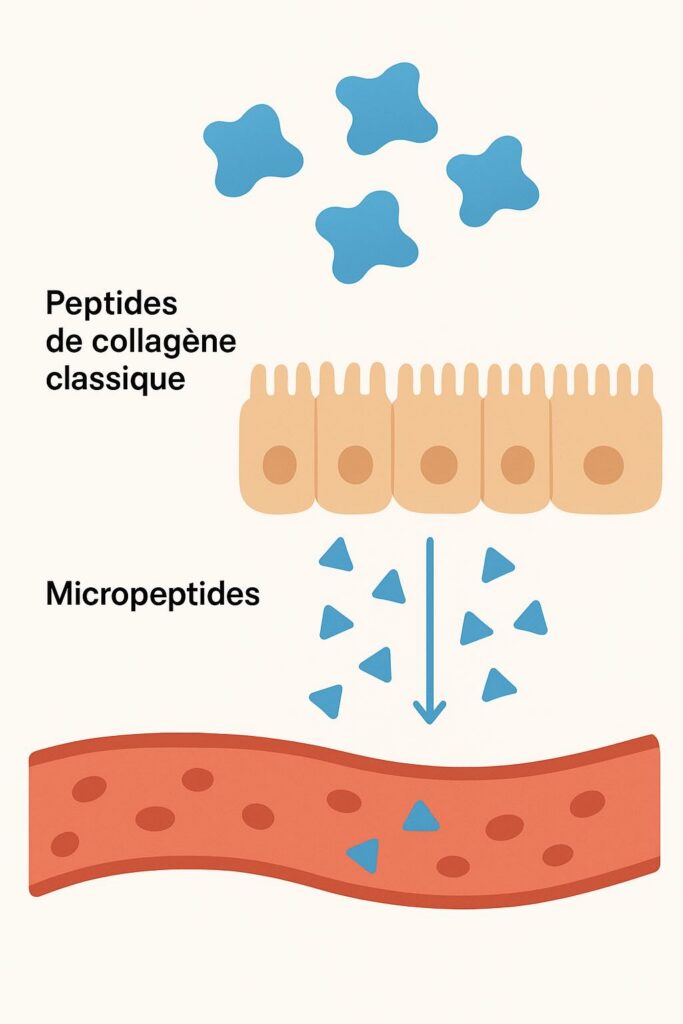

Le problème n’était pas le collagène. C’était le type de collagène.

Les molécules classiques sont trop grosses (300 000 à 400 000 Daltons) pour être absorbées. Elles traversent votre système digestif sans jamais atteindre vos articulations.

Résultat ? Vous avalez des gélules. Vous ne sentez rien. Vous abandonnez.

« Le problème des anciens collagènes, c’est qu’ils n’atteignaient jamais les articulations. Molécules trop grosses. Mal absorbées. Éliminées avant d’agir. »

Il a sorti un schéma.

« La révolution, ce sont les peptides de collagène hydrolysé. Des micro-fragments de 2 000 à 3 000 Daltons. Assez petits pour traverser la barrière intestinale, passer dans le sang, et atteindre directement le cartilage. »

« Et une fois là, ces peptides stimulent vos chondrocytes – les cellules qui fabriquent le cartilage. Ils relancent la production naturelle. Ils reconstruisent ce qui a été perdu. »